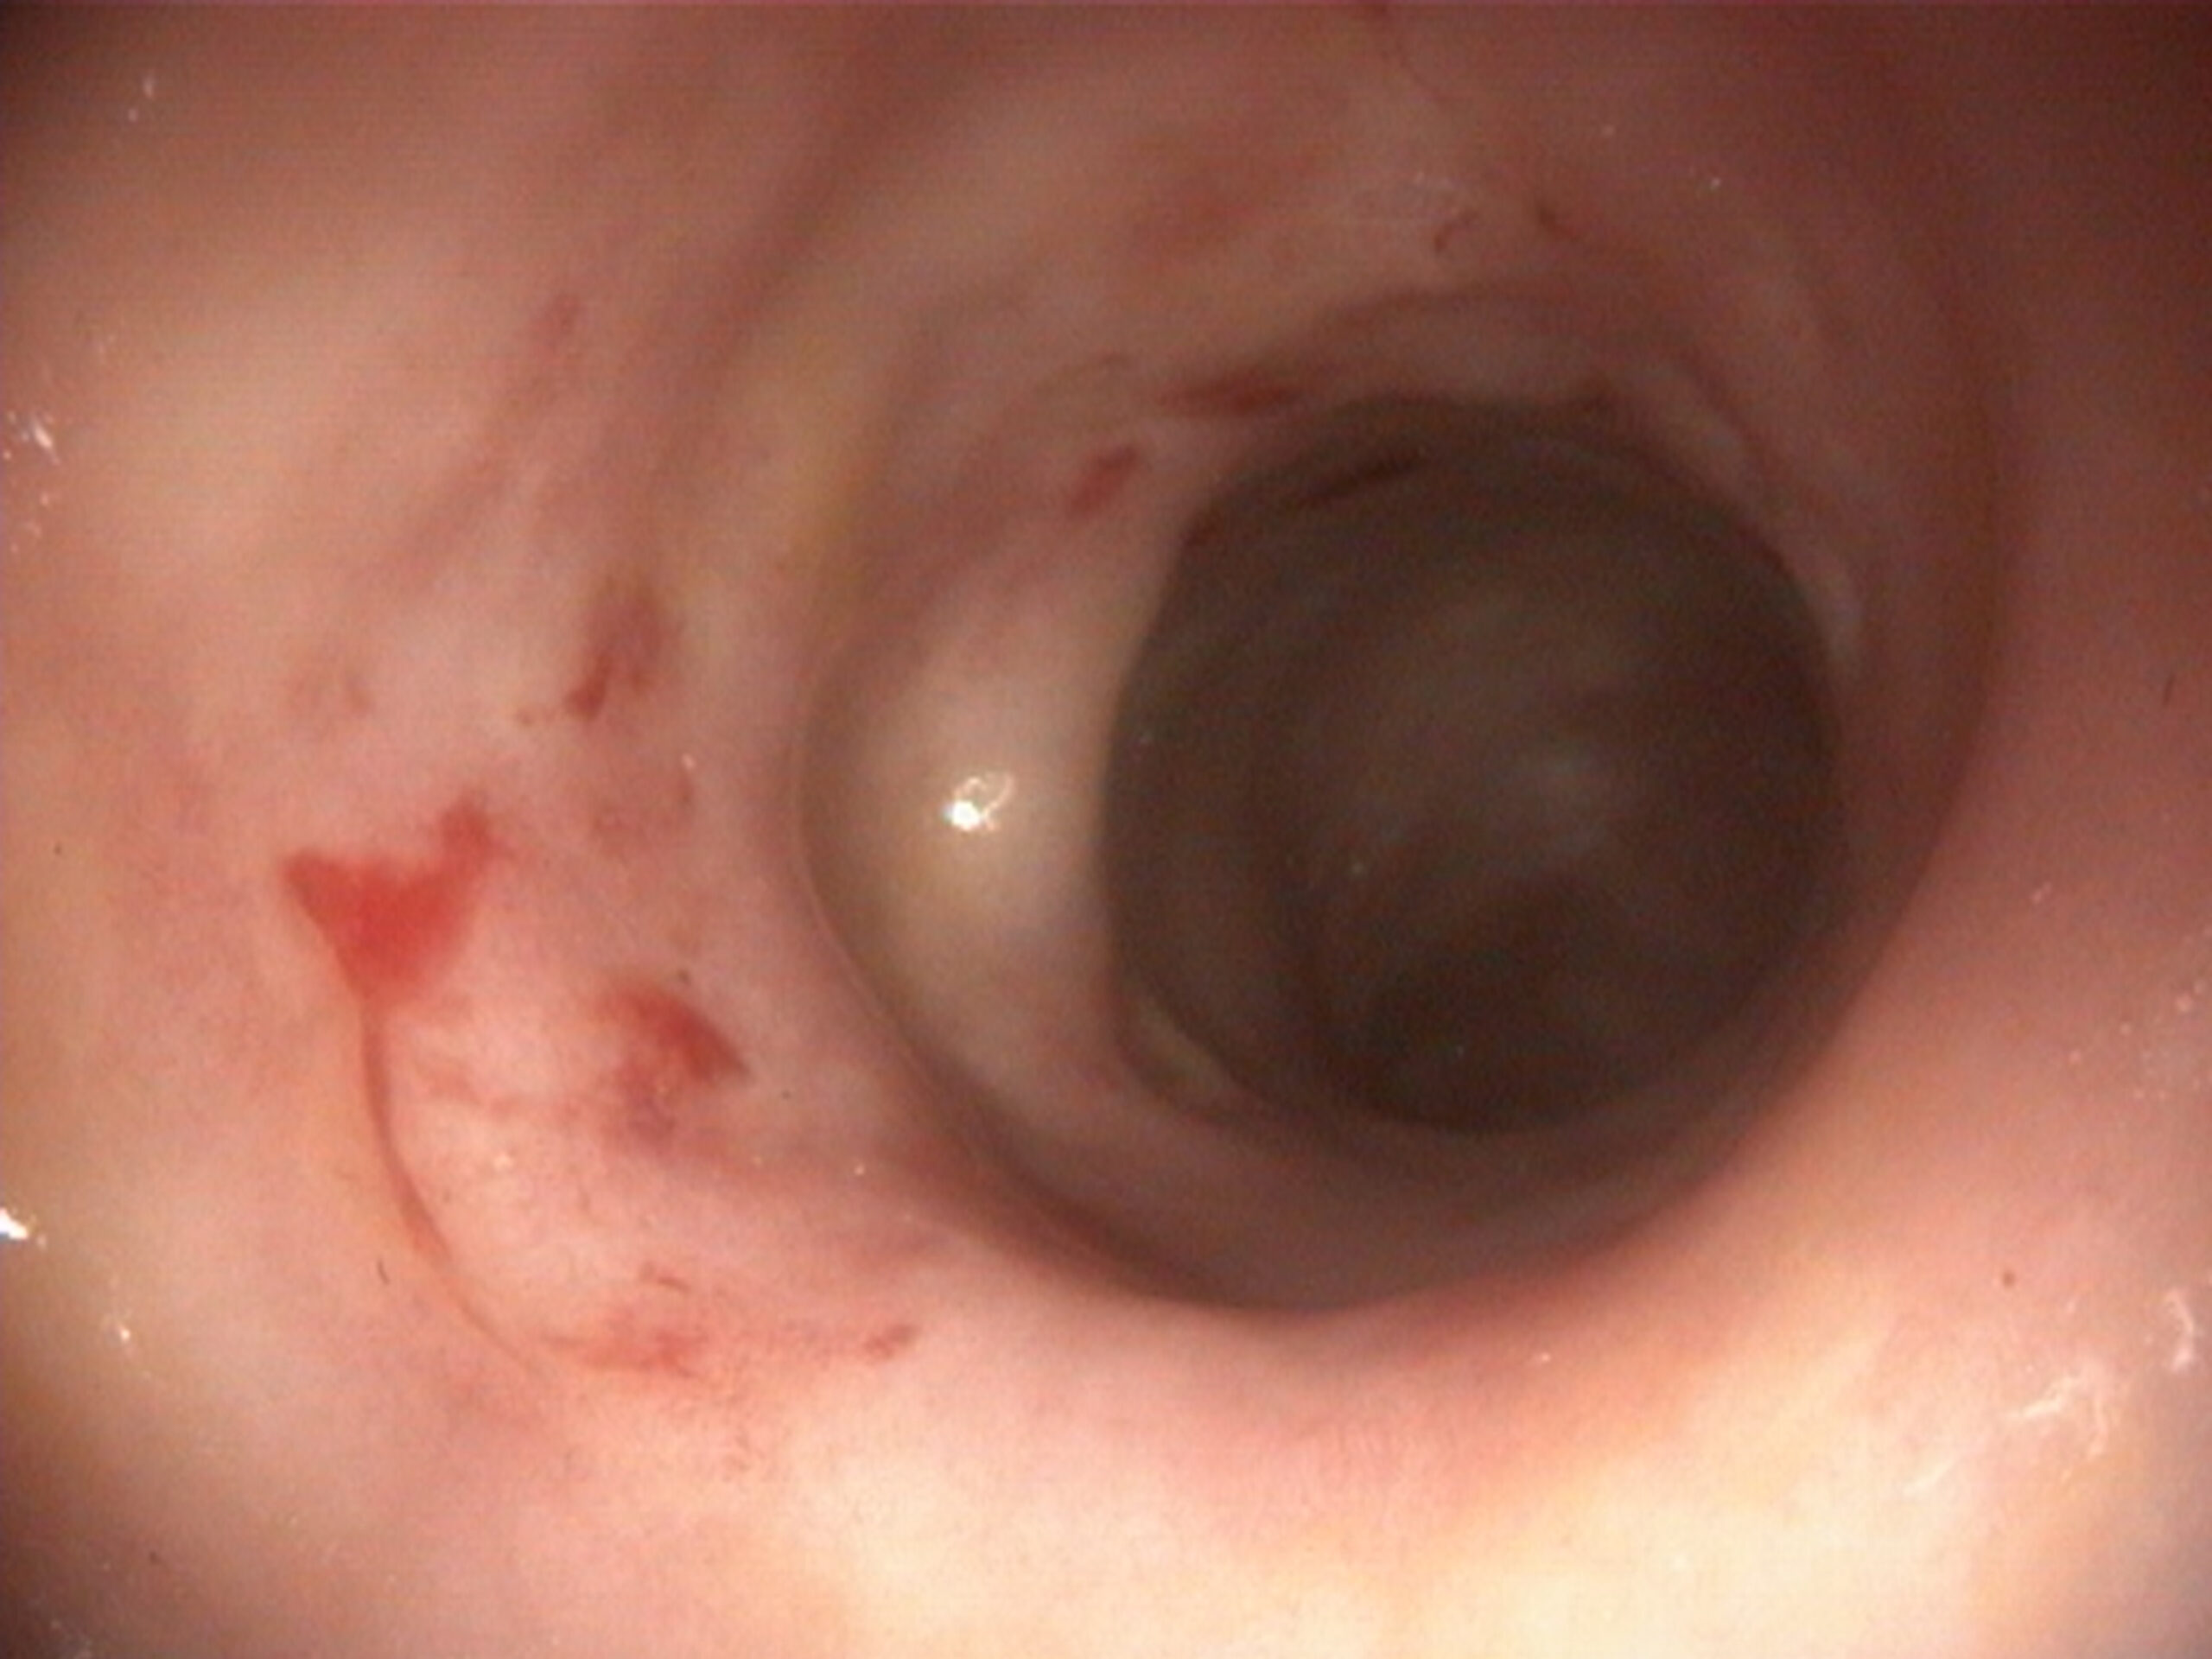

Analíticamente, destaca una anemia normocítica normocrómica no regenerativa con un hematocrito del 20 % (35 – 60 %), trombocitopenia de 43 000 plq/µL (140 000 – 520 000), leucocitosis de 22 860 leuc/µL (5 320 – 16 920), neutrofilia de 16 500 neut/µL (3 050 – 12 100) e hiperglobulinemia de 4,0 g/dL (1,6 – 3,7). En la ecografía abdominal se aprecia una marcada linfadenopatía abdominal generalizada con reacción peritoneal y esplenomegalia homogénea (Figura 1). Se realizan citologías de linfonodos mesentéricos (Figura 2).

La evaluación citológica de un linfonodo mesentérico revela un proceso inflamatorio granulomatoso asociado a infección por micobacterias, la cual se confirmó mediante una tinción de Ziehl-Neelsen y PCR en tejido (Mycobacterium avium). La micobacteriosis sistémica en perros se trata con combinaciones de un mínimo de tres antibióticos; los más empleados son los macrólidos (claritromicina o azitromicina), las fluoroquinolonas y la rifampicina. La terapia suele extenderse por varios meses, con riesgo de recaídas y desarrollo de resistencia a los antimicrobianos. El pronóstico es grave a reservado, ya que la respuesta clínica suele ser pobre. En muchos casos se considera la eutanasia debido a la dificultad de control y la afectación multisistémica.